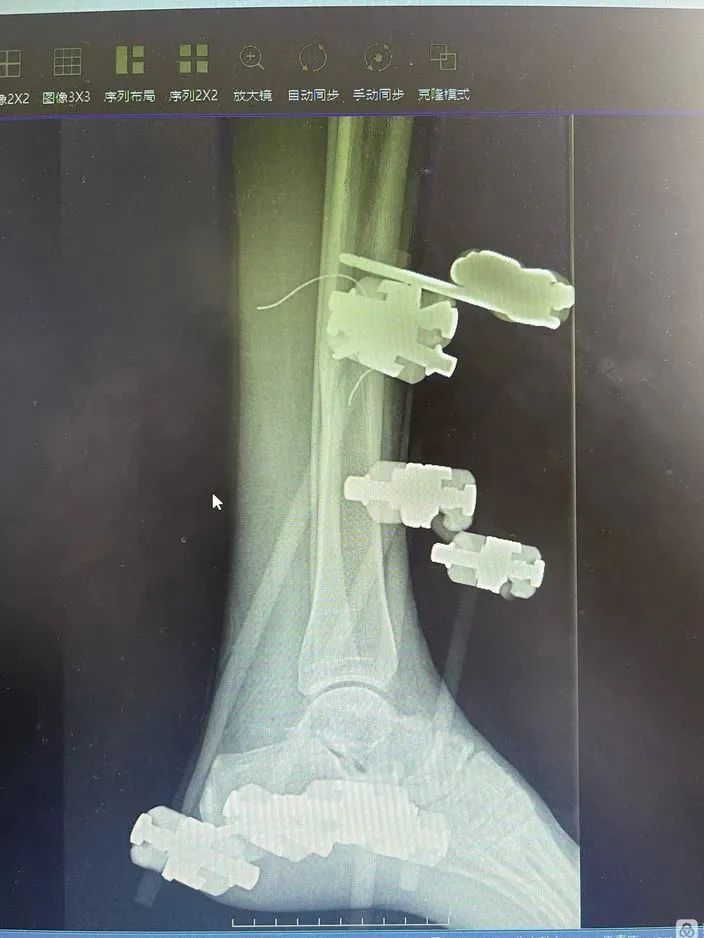

伤者刘女士,32 岁,因突发车祸,导致左踝部不完全离断。入院后,急诊诊断和影像显示,刘女士左踝部不完全离断,距骨游离,外侧软组织缺损、挫伤,胫腓韧带、跟腓韧带、距腓韧带、外侧副韧带等断裂,胫前动脉撕裂,肢体远端循环差。

「三十二岁,正是人生的黄金时期,不能让她把后半生全放在轮椅上,」在急诊科、麻醉科、手术室等多学科密切配合下,以最短的时间,为伤者进行了一期保肢手术(扩创术+韧带修复术+胫前血管吻合术+外固定架固定术+VSD 覆盖创面术)。

随着韧带、血管、神经被一根根微不可见的缝合线慢慢缝合、修复,严重内扣的脚掌被复位、固定,原本苍白的左脚逐渐恢复血色,手术室的所有人都松了一口气,刘女士的左脚,保住了!

一期手术不仅为刘女士保住了左脚,同时也为二期手术埋下了伏笔,以 VSD 装置对伤口进行封闭负压引流,既避免了大面积创口可能产生的术后感染,减轻伤者换药的痛苦,又能增加创面血供,促进肉芽生长,为二期手术创造有利条件。